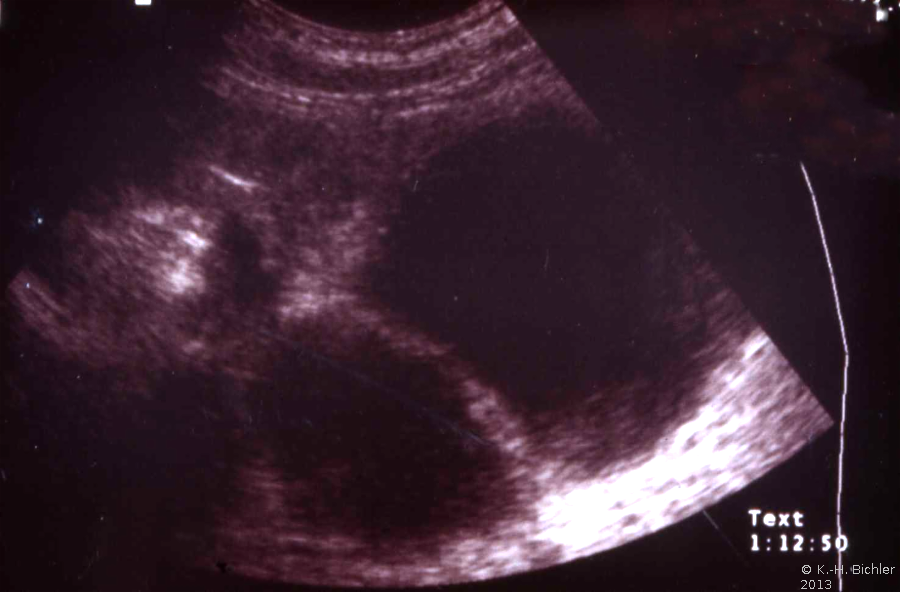

Als Komplikation ausgedehnter Mündungsdivertikel kommt es zu Abflussbehinderungen mit entsprechender Beeinträchtigung der Nierenfunktion. Als Beispiel die Harnstauungsniere bei einem Erwachsenen mit Abflussbehinderung durch ein ausgedehntes Mündungsdivertikel. Zunächst Harnableitung, dann Divertikelabtragung und Reimplantation (Abbildung HG1).